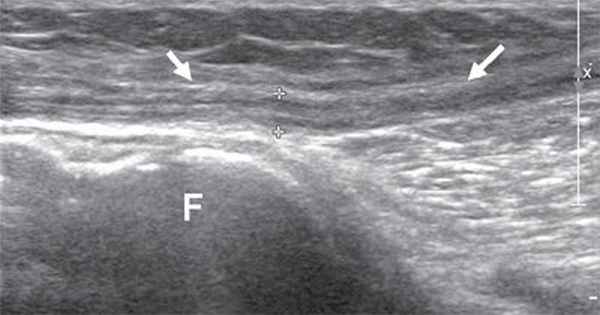

В дистальных отделах бедра, чаще в верхнем углу подколенной ямки, нерв делится на две ветви: более толстую медиальную - большеберцовый нерв и более тонкую латеральную - общий малоберцовый нерв. Именно с этой области лучше всего начинать ультразвуковое исследование седалищного нерва и его ветвей.

Общий малоберцовый нерв, отделившись от основного ствола, спускается латерально под двуглавой мышцей бедра к головке бедренной кости. В области головки малоберцовой кости нерв располагается поверхностно, прикрыт только фасцией и кожей, здесь он также хорошо доступен визуализации (рис. 5).

Рис. 5. Продольная сонограмма общего малоберцового нерва (стрелки) на уровне головки малоберцовой кости (F).

Далее общий малоберцовый нерв проникает в толщу проксимального отдела длинной малоберцовой мышцы и делится на две свои конечные ветви - поверхностный малоберцовый нерв и глубокий малоберцовый нерв. Визуализация конечных ветвей общего малоберцового нерва затруднена из-за их малого диаметра и отсутствия анатомических маркеров при их прохождении в толще мышц голени. Поверхностный малоберцовый нерв делится на конечные ветви (тыльные ветви стопы) на латеральной поверхности нижней трети голени. Глубокий малоберцовый нерв переходит на переднюю поверхность голени и здесь, располагаясь латерально, сопровождает передние малоберцовые сосуды. На тыл стопы нерв попадает под нижним удерживателем разгибателей и под сухожилием длинного разгибателя I пальца. Здесь он делится на концевые ветви. Для визуализации общего малоберцового нерва и его ветвей удобнее использовать датчики с частотой 9-17 МГц.